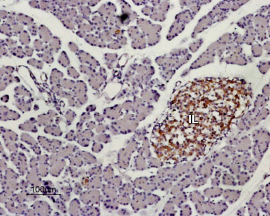

Expression of KISS1R in rat pancreasImmunohistochemical staining of paraffin embedded section of rat pancreas using Anti-KISS1 Receptor (GPR54) (extracellular) Antibody (#AKR-001), (1:100). KISS1R staining (brown) appears in Isles of Langerhans (IL). Hematoxilin is used as the counterstain.